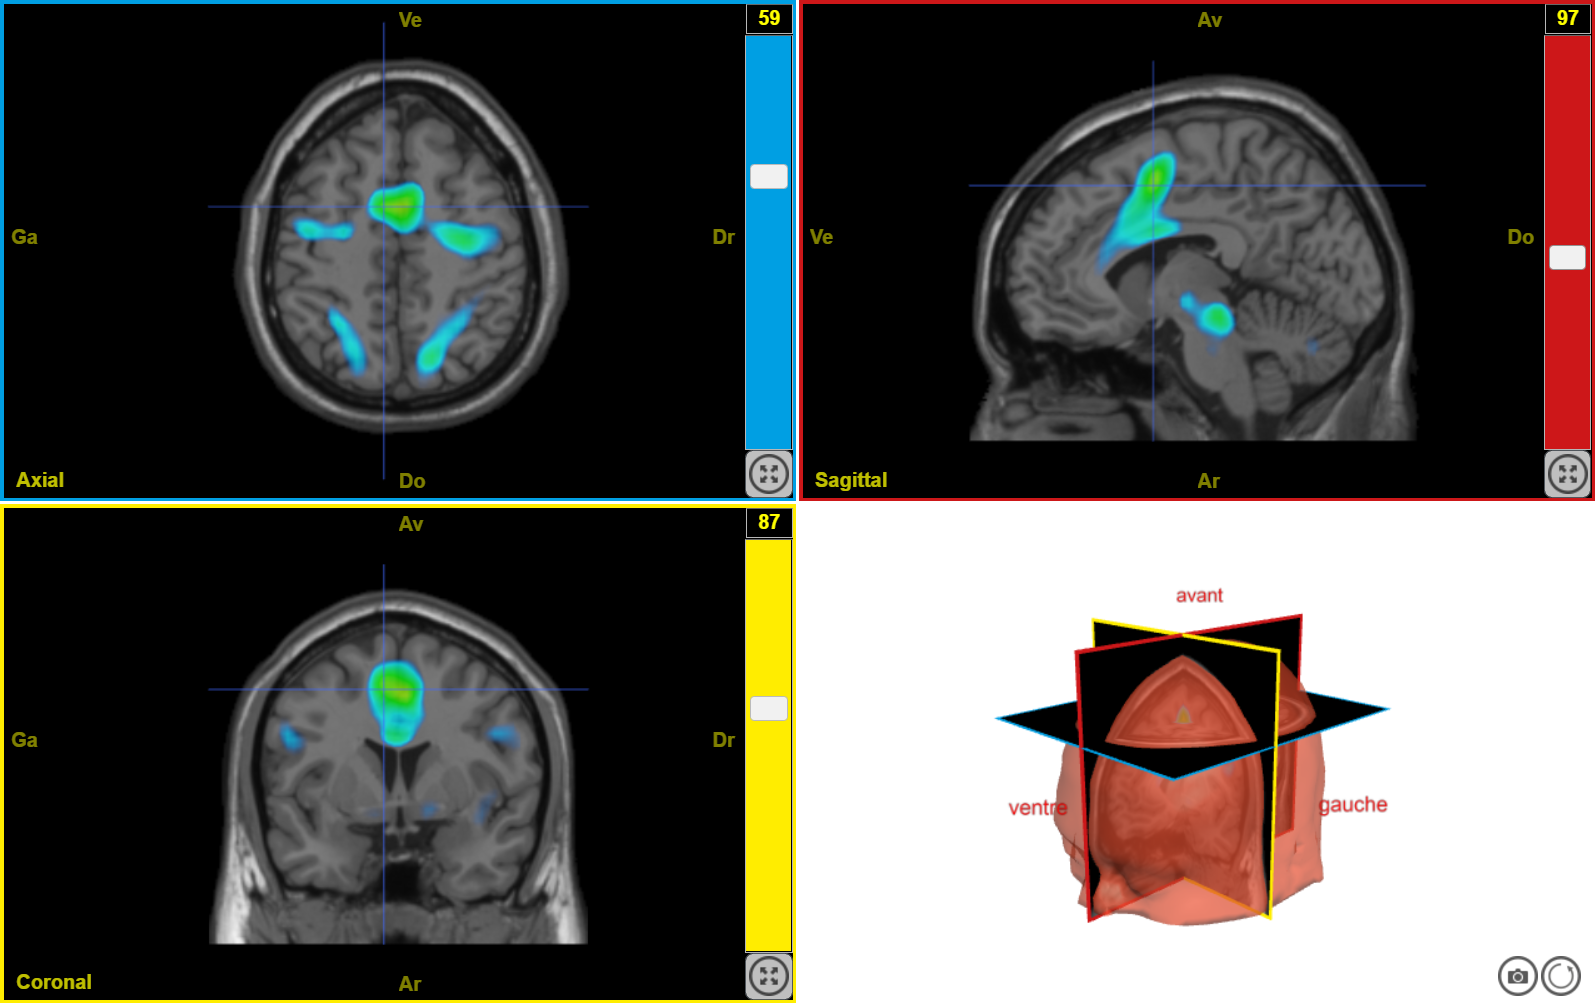

plaisir3

Image dans sa taille originale :

407 ko